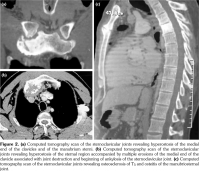

Laboratory examination revealed a slightly elevated C-reactive protein level (16 mg/L) and erythrocyte sedimentation rate (40 mm). Serum levels of calcium, albumin and phosphorus were within the normal range. Blood cell counts, liver tests, and renal function were unremarkable. Blood cultures, urinanalysis, tumor markers, and serodiagnosis for brucella were negative. Tuberculosis skin test was negative. Spine magnetic resonance imaging showed low T1, high T2 signal and contrast enhancement in the T4/T5 and L3 vertebral body and in the T4/T5 disk (Figure 1). Sacroiliac joints were normal. Computed tomography-guided biopsy of the T4/T5 disc demonstrated nonspecific inflammation and culture of this specimen was negative. Computed tomography scan of the sternoclavicular joints revealed hyperostosis and erosions involving the sternum as well as medial end of clavicle (Figure 2). Clavicular biopsy showed irregular sclerotic trabeculae. Human leukocyte antigen B27 typing was positive.

In our patient, the diagnosis of spondylodiscitis related SAPHO syndrome was established based on the medical history of palmoplantar pustulosis and computed tomography-guided biopsy which showed negative results for metastatic tumor or infection associated with hyperostosis, erosions involving sternum and medial end of clavicle and the presence of human leukocyte antigen B27. Indeed, in adults with SAPHO syndrome, prevalence of the human leukocyte antigen B27 is high and varies between 13 to 30%.(1) In our patient, the main differential diagnosis was ankylosing spondylitis. However, the medical history of palmoplantar pustulosis and the presence of hyperostosis involving sternum and medial end of clavicle were against this diagnosis. The involvement of the sternoclavicular joint is uncommon, occurring in less than 4% of patients with ankylosing spondylitis.(8)